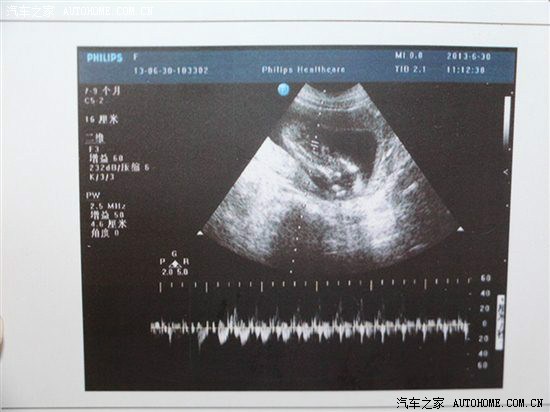

【宝宝4个月时B超留念】